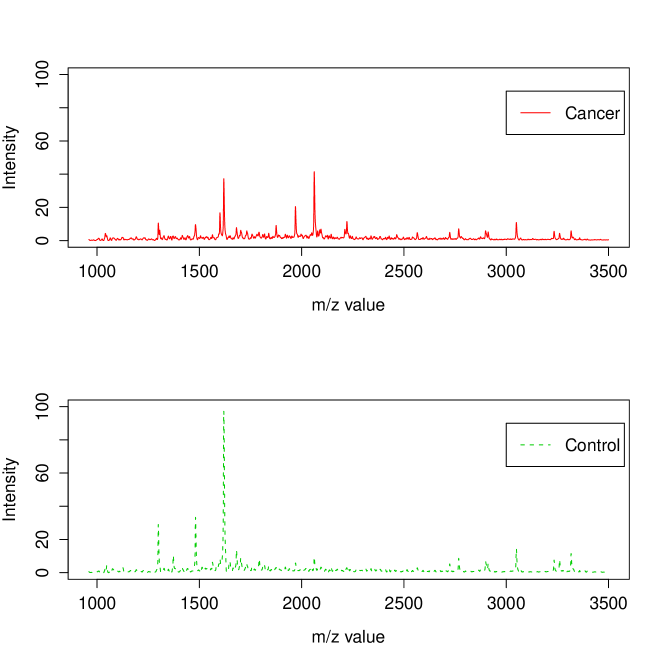

Following the experimental protocol of [3], Fisher-EM was applied on the 6 168 dimensions corresponding to m/z ratios between 960 and 3 500 Da since there is no discriminative information on the reminder. Figure 8 shows the mean spectra of the cancer and control classes estimated by Fisher-EM on the m/z interval 900–3500 Da. To be able to compare the clustering results of Fisher-EM, PCA-EM and mixture of PPCA (Mixt-PPCA) have been applied to this subset as well. It has been asked to all methods to cluster the dataset into 2 groups. It is important to remark that this clustering problem is a problem and, among the model-based methods, only these three methods are able to deal with it (see Section 4.6).

Table 7 presents the confusion tables computed from the clustering results of PCA-EM, mixture of PPCA and Fisher-EM. On the one hand, PCA-EM has selected principal axes with the 90% variance rule before to cluster the data in this subspace and mixture of PPCA has selected principal axes for each group. On the other hand, Fisher-EM has estimated the discriminative latent subspace with axis to cluster this high-dimensional dataset. It first appears that PCA-EM and mixture of PPCA provide satisfying clustering results on such a complex dataset. However, it is disappointing to see that the PCA-EM make a significant number of false negatives (cancers classified as non-cancers) since the classification risk is not symmetric here. Conversely, mixture of PPCA and Fisher-EM provide a better clustering results both from a global point of view (respectively 89% and 91% of clustering accuracy) and from a medical point of view since Fisher-EM makes significantly less false negatives with an acceptable number of false positives.

More importantly, Fisher-EM provides information which can be interpreted a posteriori to better understand both the data and the phenomenon. Indeed, the values of the estimated loading matrix , which is a matrix here, expressed the correlation between the discriminative subspace and the original variables. It is therefore possible to identify the original variables with the highest power of discrimination. It is important to highlight that Fisher-EM extracts this information from the data in a unsupervised framework. Figure 9 shows the correlation between each original variable and the discriminative subspace on an arbitrary scale. The peaks of this curve correspond to the original variables which have a high correlation with the discriminative axis estimated by Fisher-EM.

Figure 10 plots the difference between the mean spectra of the classes cancer and control (cancer - control) and indicates as well, using red triangles, the most discriminative original variables (m/z values). It is not surprising to see that original variables where the cancer and control spectra have a big difference are among the most discriminative. More surprisingly, Fisher-EM selects the original variables with m/z values equal to 2800 and 3050 as discriminative variables whereas the difference between cancer and control spectra is less for these variables than the difference on the variable with m/z value equal to 1350. Such information, which have extracted from the data in a unsupervised framework, may help the practitioner to understand the clustering results.